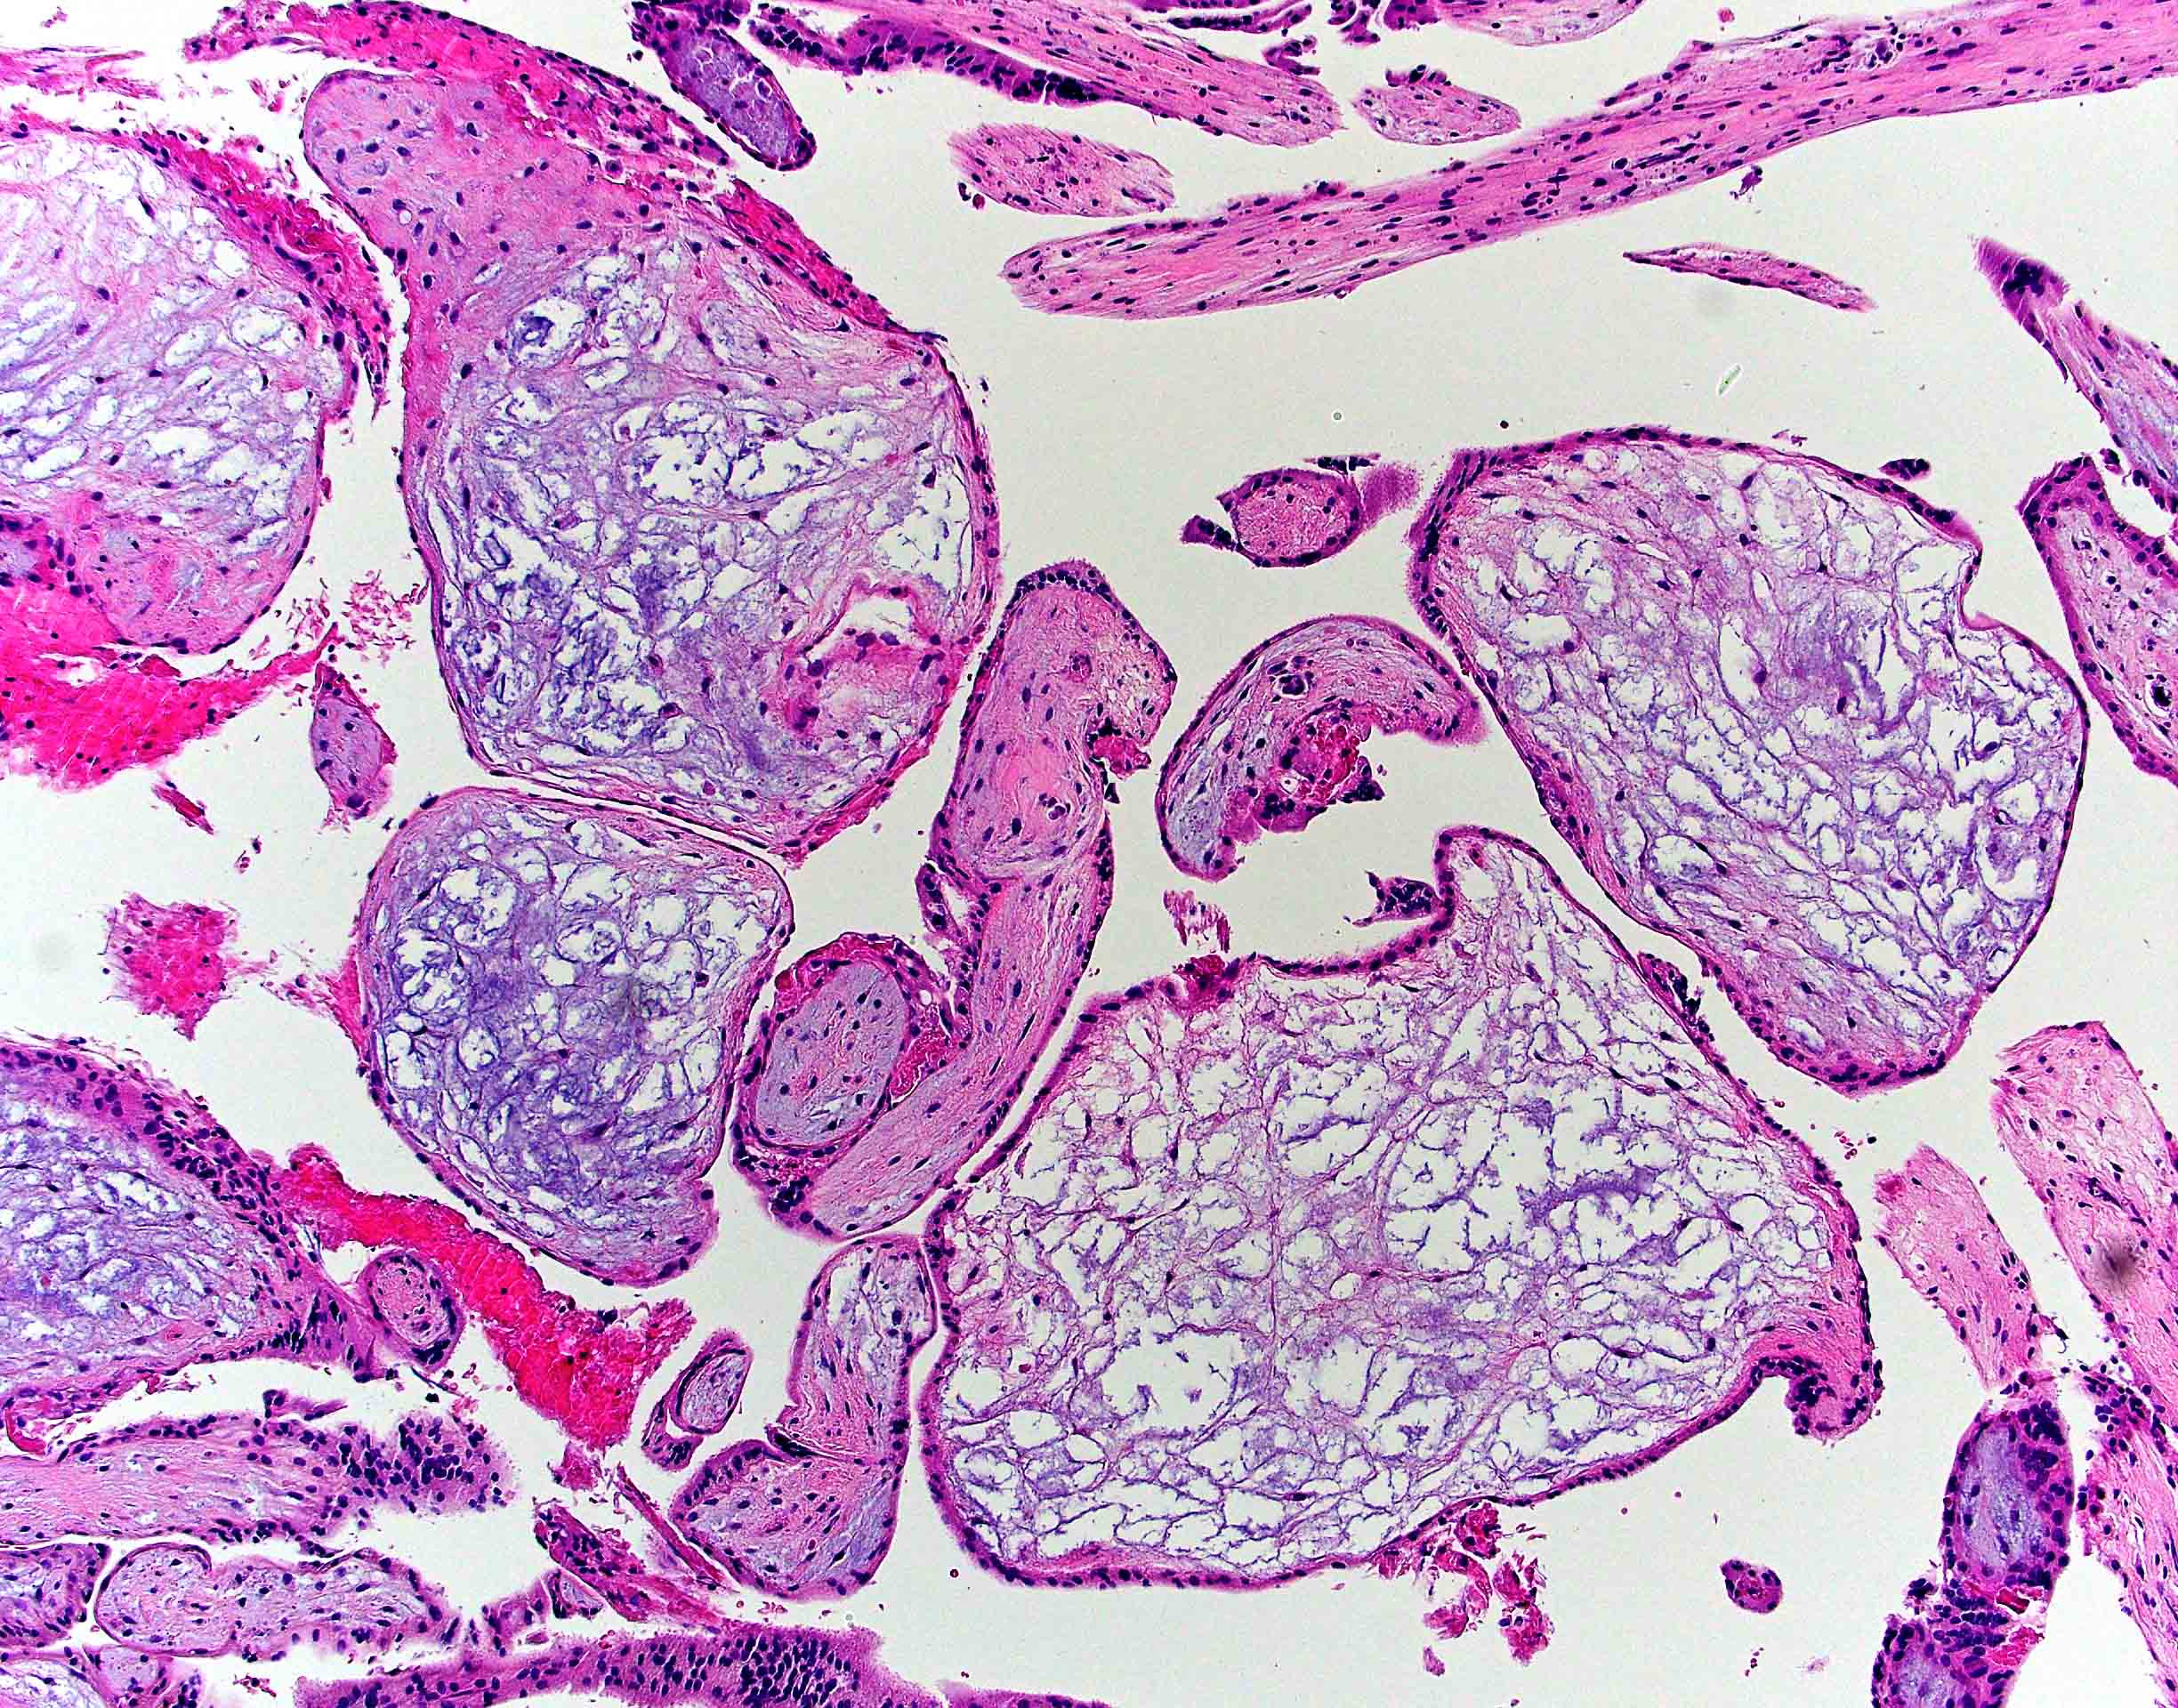

Microscopic (histologic) description

- Removed or passed products of conception may contain:

- Early first trimester chorionic sac (< 8 weeks): thin chorion and scant villi that are sparsely or nonvascularized

- Villous trophoblast is bilayered (mononuclear cytotrophoblast inner layer and multinucleated syncytiotrophoblast outer later) and circumferential with occasional polarized trophoblast protrusions

- Mid first trimester chorionic sac (8 - 10 weeks): may exhibit recognizable amnion, early stromal collagenization of chorion and proximal villi and increased volume of distal villi with distinct capillaries

- Later first trimester chorionic sac (> 10 weeks): may exhibit loose fusion of amnion and chorion, a more collagenized chorion and stem villi, more distinct walls of fetal vessels and numerous villi with increasing demarcation between proximal and distal branches

- Spectrum of villous changes in immature chorionic villi following embryonic death (Placenta 2005;26:114):

- Cellular debris within villous vessels - earliest change

- Villous edema with myxoid stromal degeneration - may be confused with molar gestation

- Collagenized avascular villi (villous sclerosis / fibrosis)

- Villous edema and sclerosis / fibrosis often coexist

Microscopic (histologic) images

Contributed by Chrystalle Katte Carreon, M.D. and Drucilla J. Roberts, M.D.